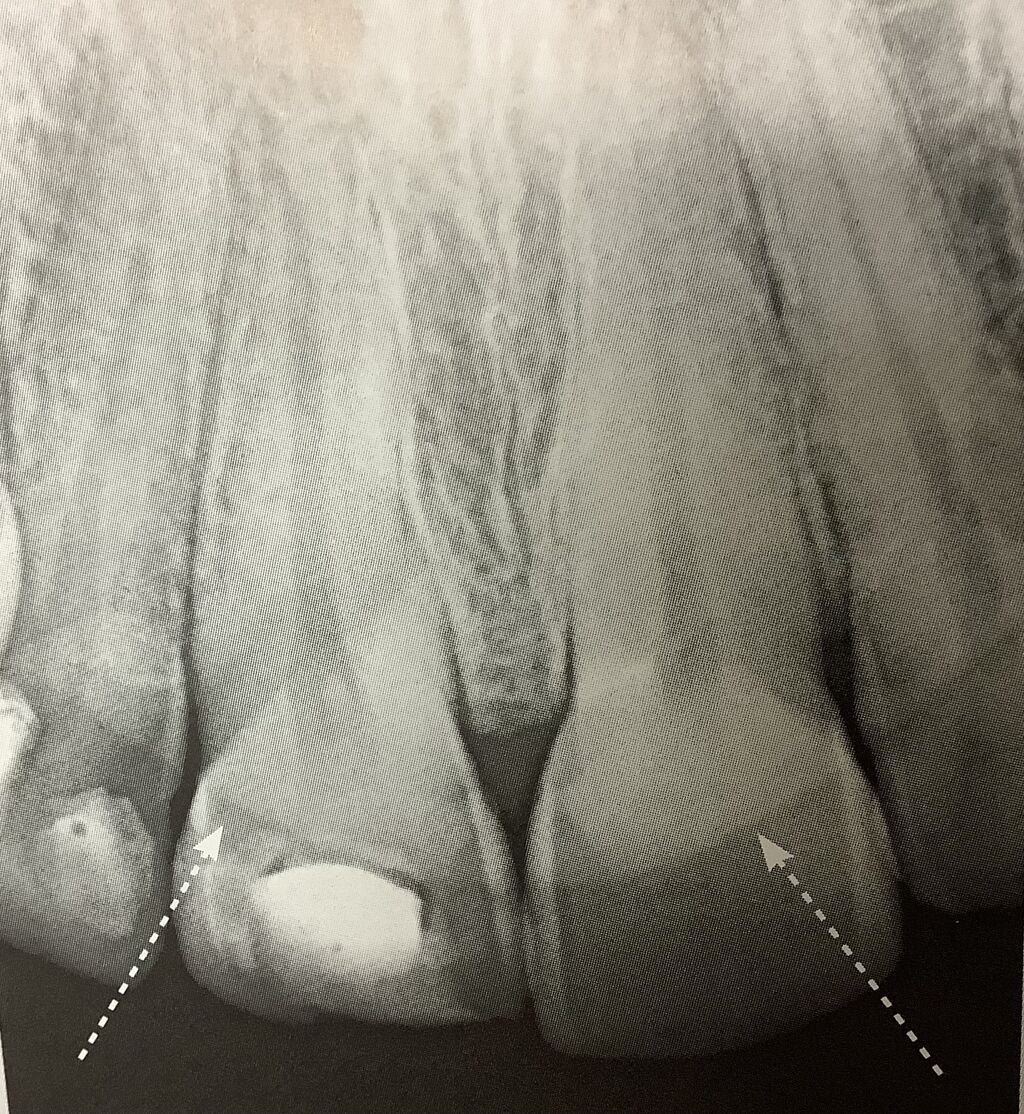

鼻が前歯のレントゲンに重なって見えています。

矢印です。

お肉なんで、薄いフィルターみたいな感じ。

歯のヒビを見つける時は、注意ですよね。